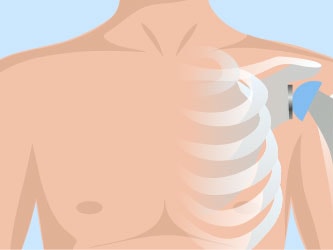

Shoulder Replacement: How Can We Speed Up Recovery?

Shoulder arthroplasty rehabilitation requires attention to the entire kinetic chain. From the acute stage through home care, the clinician needs to prepare the patient for outpatient rehab. The first 21 days should focus on preoperative impairments of posture, scapular mobility, and restrictors to shoulder elevation. This will be the bridge to recovering the ADL, and eventually functional strength.

One of the key rehabilitation goals to return patients to their desired activity is to eliminate and prevent the dreaded shoulder hike or shrug following shoulder replacement. We can do a better job of addressing this concern and it should be every clinicians goal when rehabbing a shoulder patient.

The biomechanical reason for the dreaded shoulder hike or shrug is that most shoulder replacement patients have pre-operative rotator cuff weakness or pathology. If the rotator cuff cannot adequately compress the head of the humerus into the glenoid fossa, the force couple will be absent between the rotator cuff and the deltoid, meaningthe head of the humerus will go into a superior direction versus a posterior inferior direction. The exercises using a short lever deltoid action can result in making the deltoid a two-action muscle (performing both humeral head compression and elevation), thus addressing the shoulder hike or shrug!